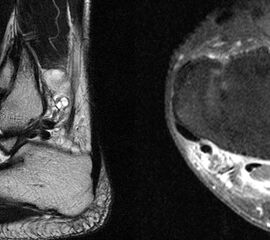

Die Magnetresonanztomographie erlaubt nicht nur die exakte Beurteilung der intramedul­lären und extraossären Tumorausdehnung einschließlich reaktiver Zone, sondern auch die genaue Lagebeziehung zu neurovaskulären Strukturen (Abb. 8) und eine Differenzierung zwischen vitalen versus nekrotischen Tumoranteilen. Dies ist insbesondere für eine mögliche Biopsie von entscheidender Bedeutung um repräsentatives Tumorgewebe für die histo­patho­logische Analyse gewinnen zu können. Die bei Verdacht auf einen Knochen- oder Weichteiltumor vom Radiologen durchzuführenden Standardprotokolle der MRT wurden im Jahr 2006 von der Arbeitsgemeinschaft Muskuloskelettale Diagnostik der Deutschen Röntgengesellschaft veröffentlicht (Tab.2) und gewähren bei entsprechender Umsetzung eine qualitativ hochwertige Untersuchung (DRG, 2006).

Stellvertretend für gutartige tumoröse Weichteilgeschwulste soll hier die pigmentierte villo-noduläre Synovialitis (PVNS) als wohl häufigste gutartige Weichteilneoplasie des Fußes erörtert werden. Die PVNS nimmt als einzige Entität in allen größeren Studien zu Fußtumoren einen der drei vorderen Plätze ein. Als Synonym der extra-artikulären Form der PVNS ist der Begriff des teno-synovialen Riesenzelltumors gebräuchlich. Die sehnenscheiden- und gelenkkapselreiche Fußanatomie prädestiniert für die Entstehung einer PVNS (Abb. 32). Das weibliche Geschlecht ist doppelt so häufig betroffen, das bevorzugte Alter liegt zwischen 30-50 Jahren. Eine schmerzlose, nur langsam größenprogrediente Schwellung ist das häufigste Symptom. Die Rezidivrate wird mit bis zu 30% angegeben 49. Bei der PVNS handelt sich um einen fibro-histiozytären Tumor (echte Neoplasie) und nicht wie ehemals angenommen um ein inflammatorisches oder posttraumatische Geschehen. Für die intraartikuläre Form, die wiederum in eine noduläre/lokalisierte und diffuse Form unterteilt werden kann, stellt das Sprunggelenk die dritt-häufigste Lokalisation am gesamten Körper dar (Abb. 33).

Im Röntgen zeigt sich gelegentlich eine gut abgrenzbare Weichteilformation (bei nodulärer Form) und knöcherne Druckarrosionen der angrenzenden Knochen. Sekundäre arthrotische Veränderungen der angrenzenden Gelenke sind möglich. Die MRT kann mit einem stark T2-gewichtetem Gradientenecho sog. Suszeptibilitätsartefakte der Hemosiderin­ablagerungen darstellen. Diese führen gewöhnlich zu charakteristischen Signalaus­löschungen in T1 und T2 gewichteten Sequenzen. Eine Kontrastmittel-Aufnahme erfolgt in der Regel diffus und inhomogen. Die Therapie besteht in einer offenen Resektion. Wir raten dringend davon ab, intraartikuläre, lokalisierte Formen der PVNS per Arthroskopie resezieren zu wollen. Dieser Tumor sollte, wenn möglich, marginal und nicht intraläsional reseziert werden. Eine arthroskopische Zerkleinerung mit dem Shaver würde aus einer nodulären Form eine diffuse Form produzieren und die Rezidivwahrscheinlichkeit deutlich steigern. Ebenso ist vor einer Radiosynoviorthese (RSO) bei Vorliegen einer nodulären Variante abzuraten. Bei diesem nuklearmedizinischen Verfahren, welches gewöhnlich Anwendung bei chronisch entzündlichen Gelenkerkrankungen findet, werden Beta-Strahler in Gelenke injiziert. Ein therapeutischer Effekt hat sich bisher nicht nachweisen lassen.

MR-tomographische Darstellung eines unspezifischen weichteiligen Raumforderug im Bereich des dorso-lateralen Rückfußes. Die offene Probebiopsie ergab schließlich die Diagnose eines hochmalignen Synovialsarkoms.

Abbildung 34